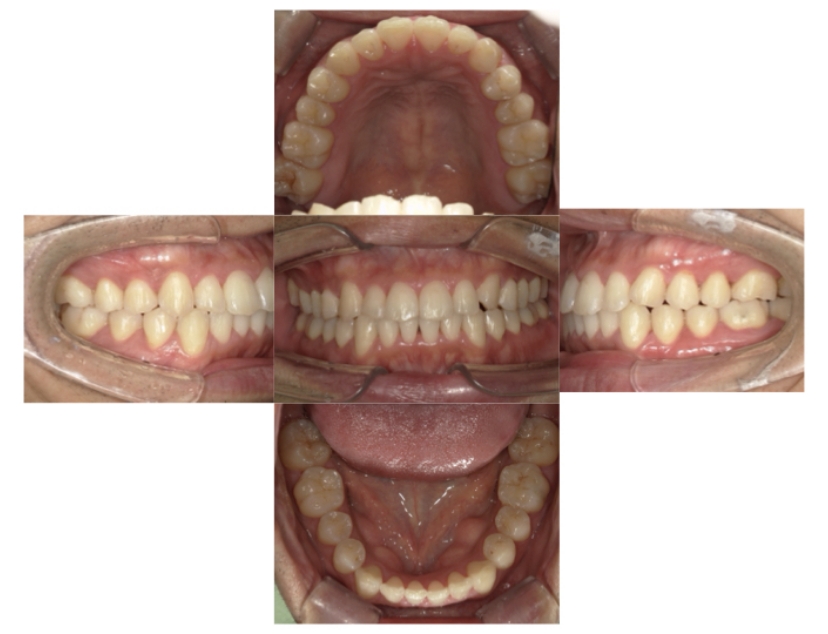

症例2

上下顎前突、叢生

抜歯

ブラケット矯正

上下顎前突、叢生(上下出っ歯、上下の前歯のガタガタ)のケースです。

装置はラビアル(上下表側)で、上下顎の小臼歯を4本抜歯を行っています。抜歯したスペースを使って、上下の前歯の後方移動と叢生(ガタガタ)の改善を行っています。

主訴 前歯のガタガタと口元がでているのが気になる。

年齢・性別 30歳 女性

お住まいの地域 東京都大田区

治療方針 抜歯スペースを利用して上前歯の叢生(ガタガタ)と口元突出の改善

抜歯部位 上下顎左右第一小臼歯

使用装置 ラビアル(上下表側)、顎間ゴム

治療期間 1年11か月

治療回数 13回

リテーナー クリアリテーナー

BEFORE

AFTER